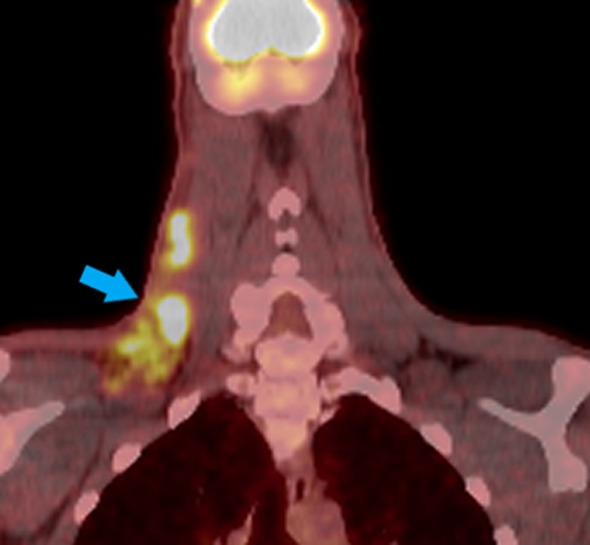

Based on imaging studies, the patient was designated as Ann-Arbor stage IIB disease (early unfavorable). The patient subsequently underwent chemotherapy with ABVD (doxorubicin, bleomycin, vinblastine and dacarbazine) with involved-site radiotherapy and achieved complete treatment response two years after initial presentation. A positron emission tomography (PET) scan two months post-treatment showed no evidence of disease consistent with clinical remission (Fig. 4). Clinically, the patient continued to have pain in both hands, fatigue, and night sweats, but denied fever, chills or further unintentional weight loss.

Fig. 4.

PET/CT with arrow indicating enlarged lymphadenopathy